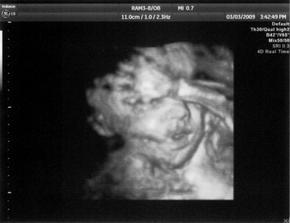

3.3. 4D ultrazvuk, moc hezký zážitek, mimís zíval, máchal rukama a nohama 🙂 a ukázal nám pohlaví 🙂.